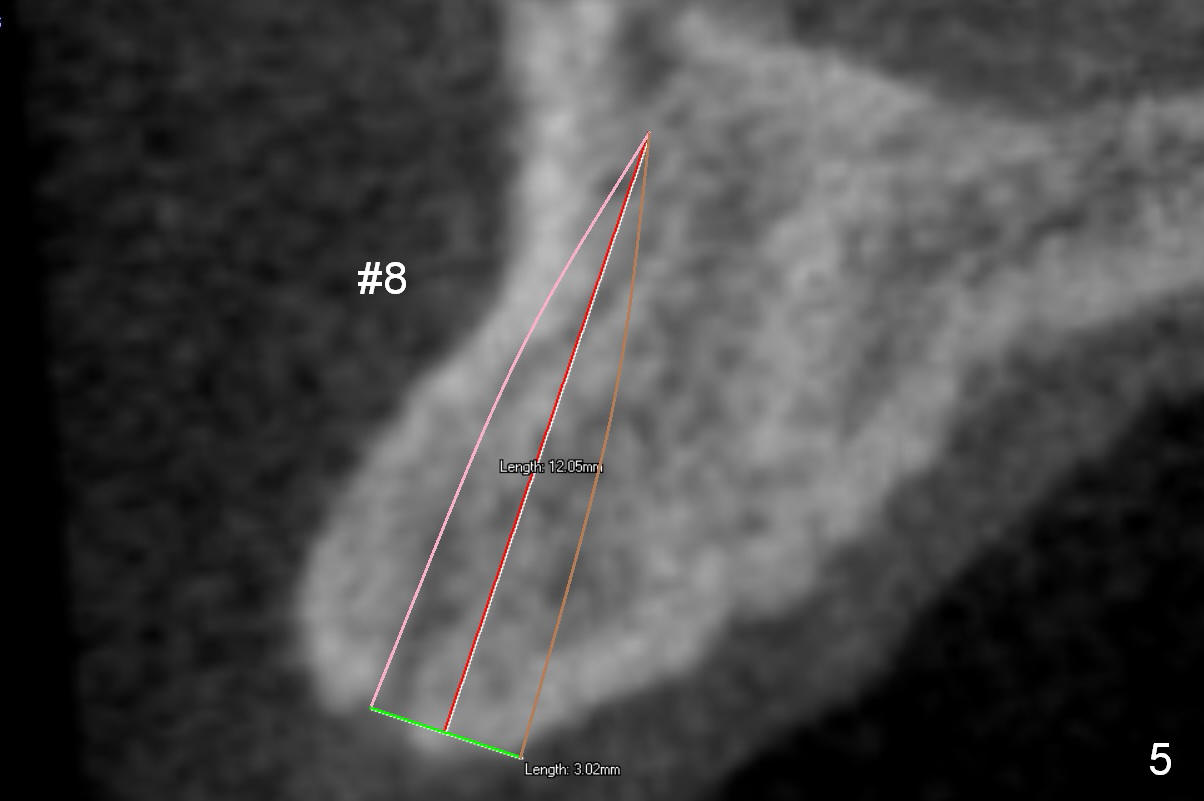

|

There are two types of implant design for the upper central incisors. The first one is to place implants as large as possible (Fig.1,2), i.e., place the implants in the middle of the alveolar bone, irrespective of the occlusion with the opposing.

The second design is to place relatively smaller implants with the occlusion in mind (Fig.3,4). The starting point for the osteotomy will be as lingual as possible (especially Fig.4). The axis of the implant will be more parallel to the buccal plate. The angles of the angled abutments will be less (Fig.1 vs. 3; Fig.2 vs. 4). The cosmetic result may be better.

For the best trajectory, osteotomy at #8 should be initiated as palatally as possible (Fig.8 *). When a 4x11 mm 2-piece implant is placed, there is possibility that the apical buccal plate may be perforated (>). In contrast, a 3x11 mm 1-piece implant is more skinny with less coronal palatal thread exposure (Fig.9). The latter will be covered with bone graft and collagen dressing.